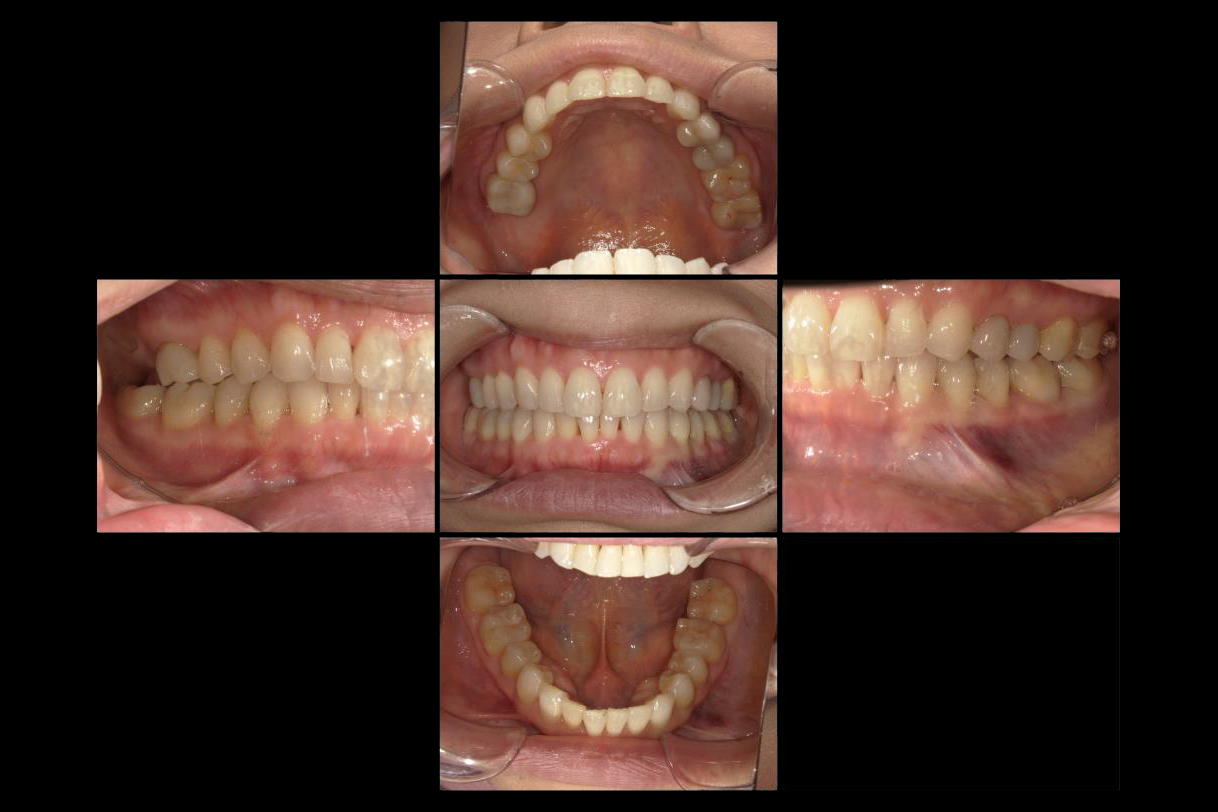

2022年9月

浜松市中区の症例紹介 マウスピース矯正

2025年9月

初診時年齢:40代男性

治療:全体矯正

治療法:マウスピース型矯正装置(インビザライン)

治療期間:3年

費用:902,000円(税込)

リスク・副作用:装置装着による違和感、歯の移動時の痛み